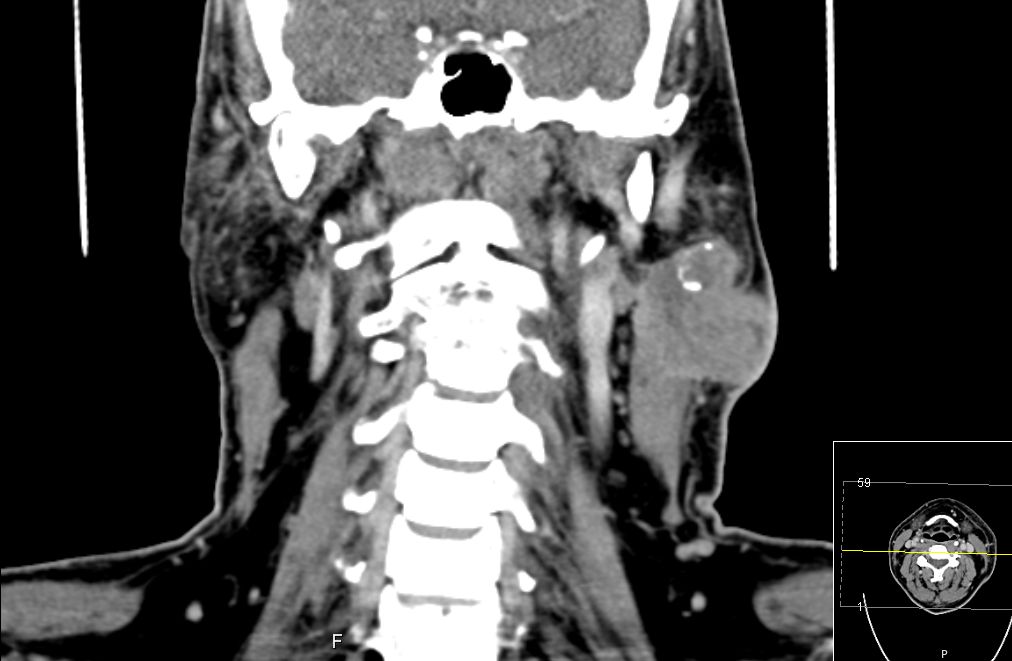

| CT | 51-jähriger Mann, der eine Gesichtsschwellung bemerkte. Adenokarzinom pT3 pN1 Mo L1 G3. Subtotale Protidektomie unter Neuromonitoring, ND LI und II links, Adjuvante RT. ![]() |